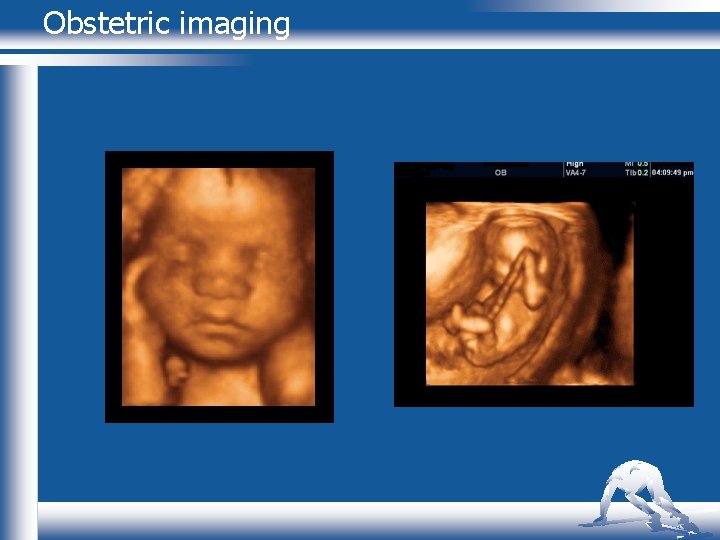

3 D ultrasound imaging n 3 D IMAGING n n n Use of 3 D ultrasound popularised by obstetric scanning. n Volume images of the fetus Some suggestion improves diagnostic capabilities n Cleft palate n Spinal defects Gynaecological pathologies n Quantify volumes in urethra and paravaginal supports Anal canal anatomy and mammography THE UNIVERSITY OF AUCKLAND DEPARTMENT OF SPORT AND EXERCISE SCIENCE

Obstetric imaging